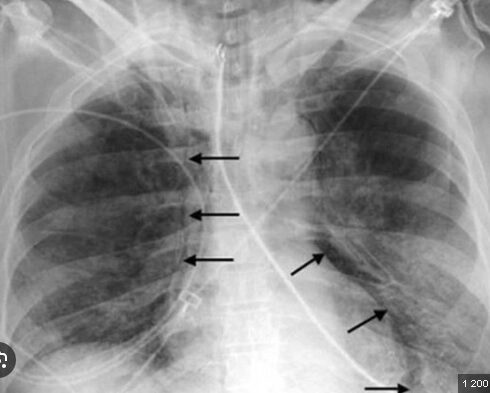

Заразяването най-често става чрез вдишване на прахови частици, съдържащи бактерията, контакт с мляко, урина, изпражнения или секрети на заразени...